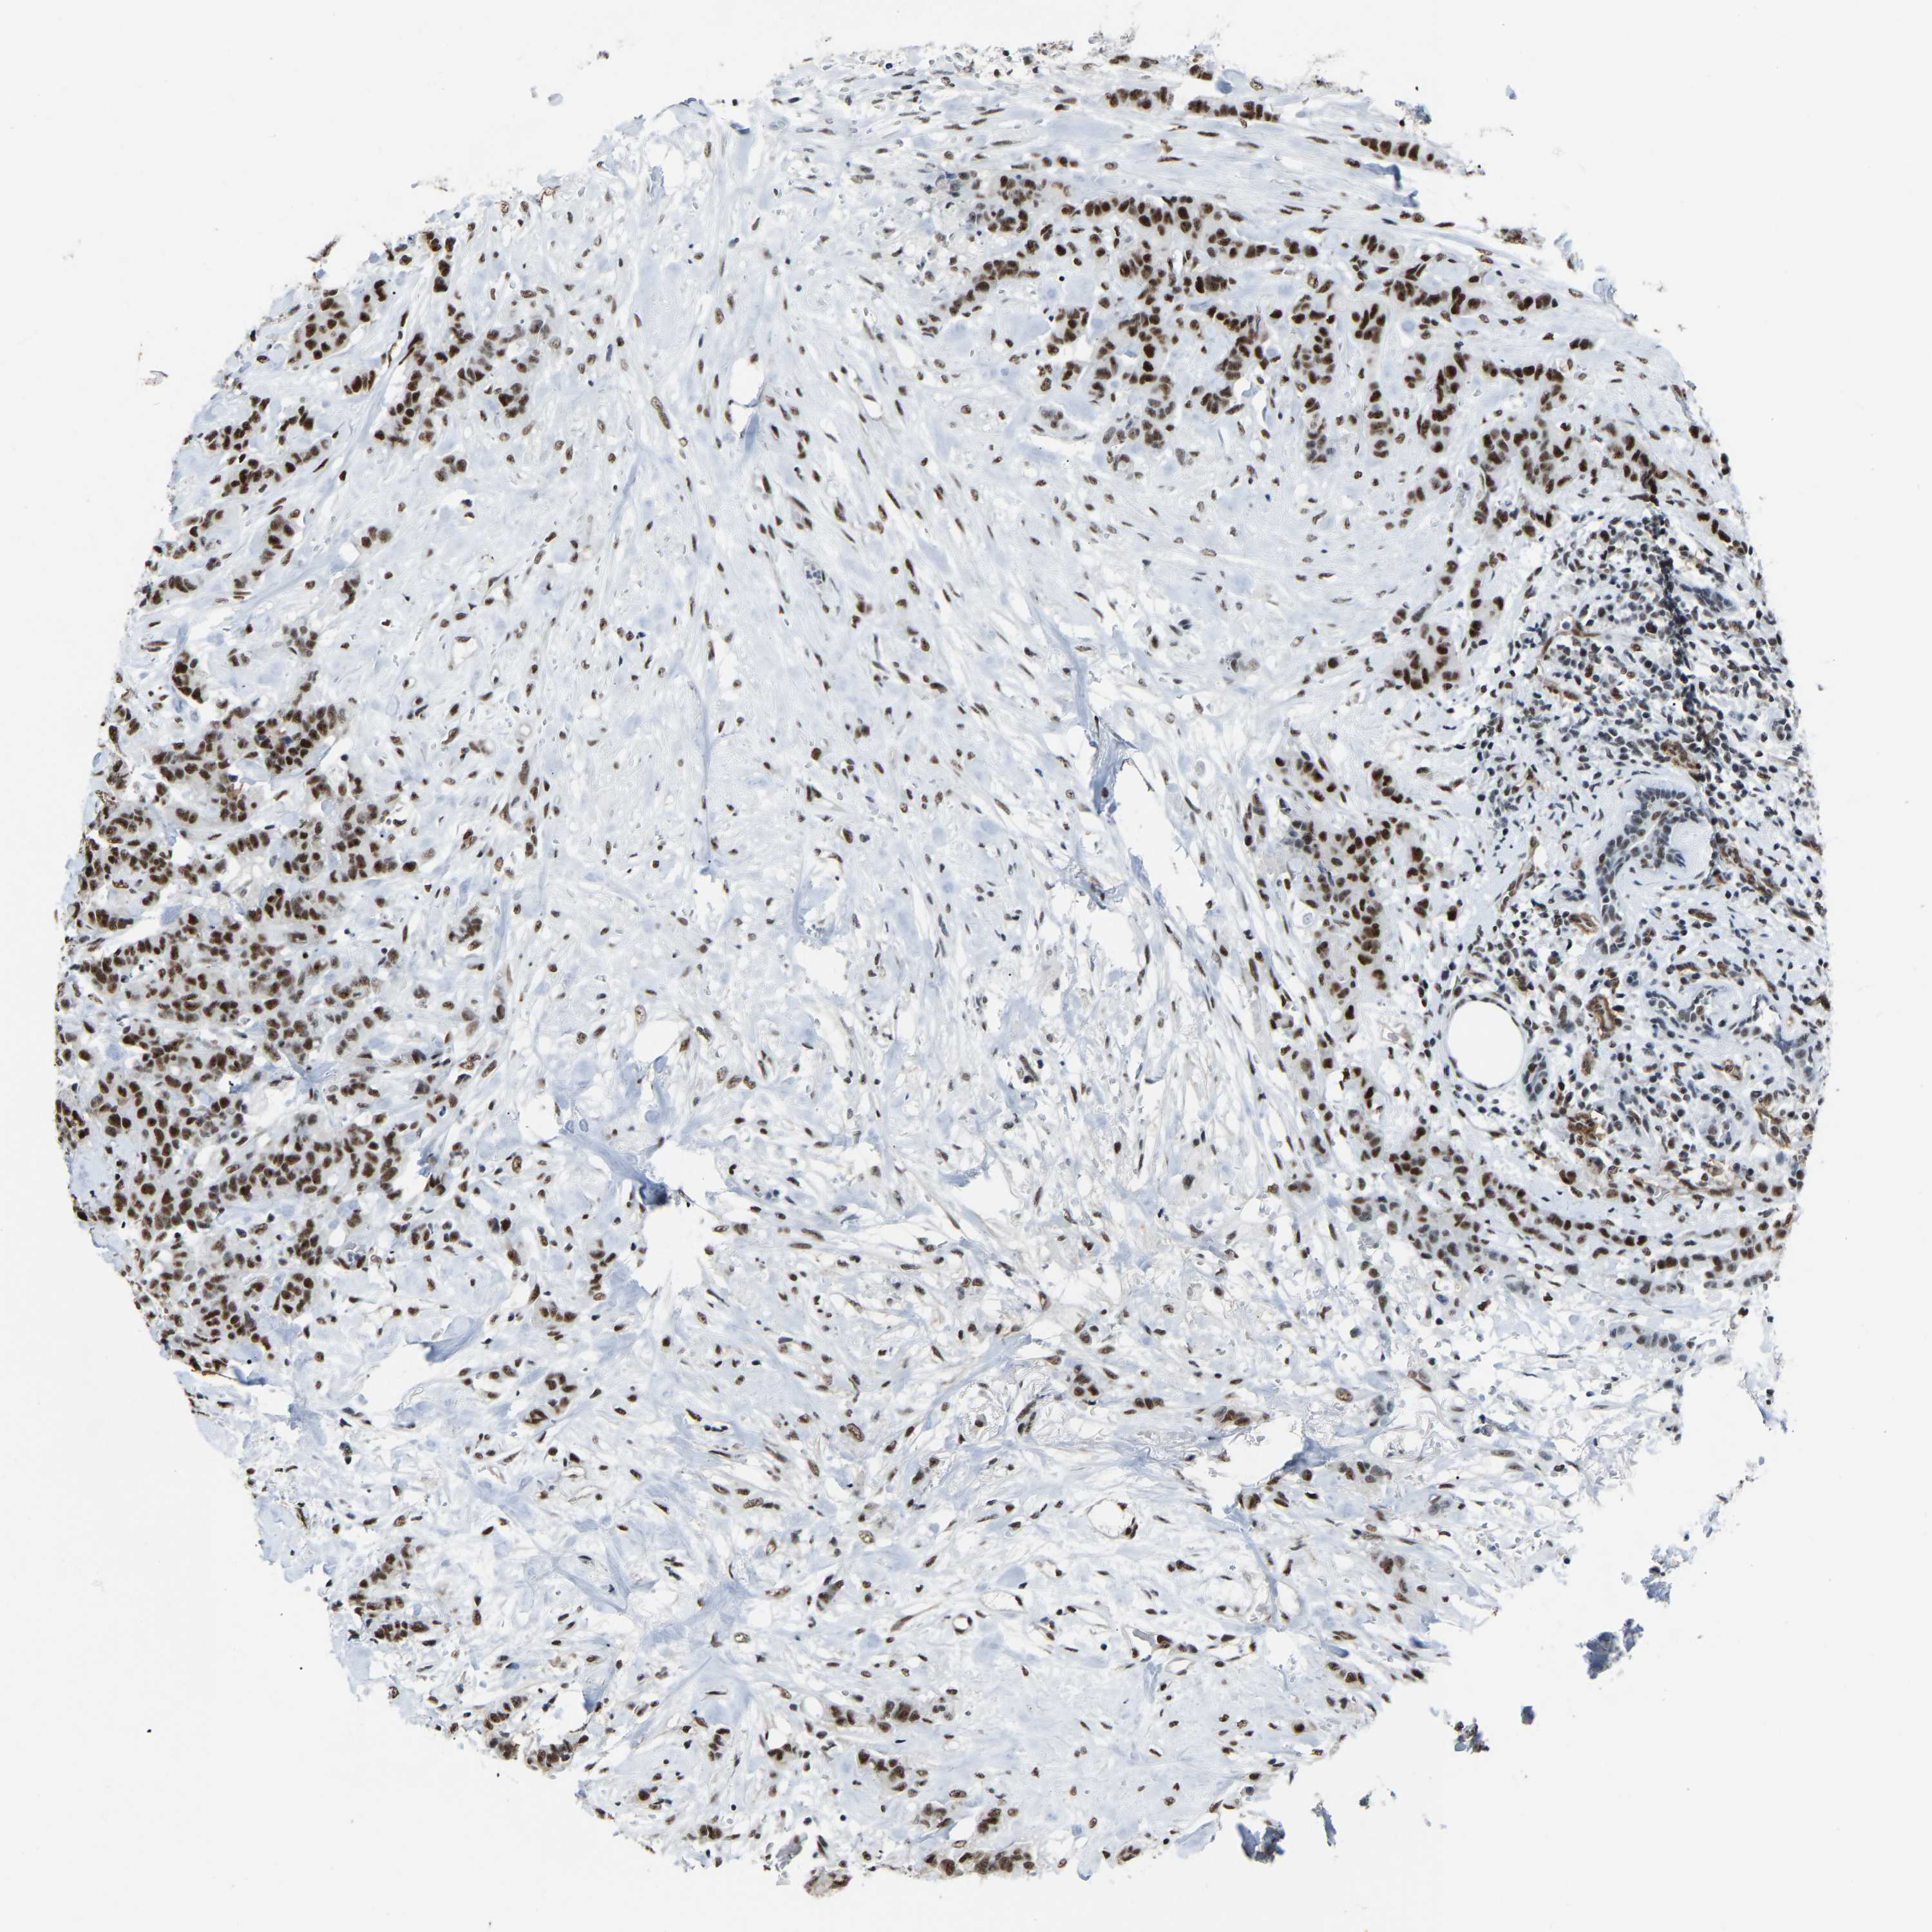

CANCER BREAST CANCER Show tissue menu

BRCA TCGA BRCA VALIDATION PROTEIN EXPRESSION